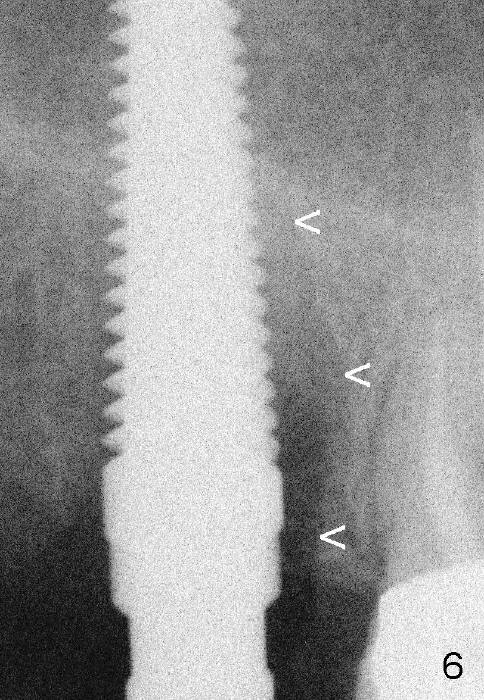

Fig.6 (intraop PA with 5 mm tap) <: mesial lamina dura of the mesiobuccal socket.